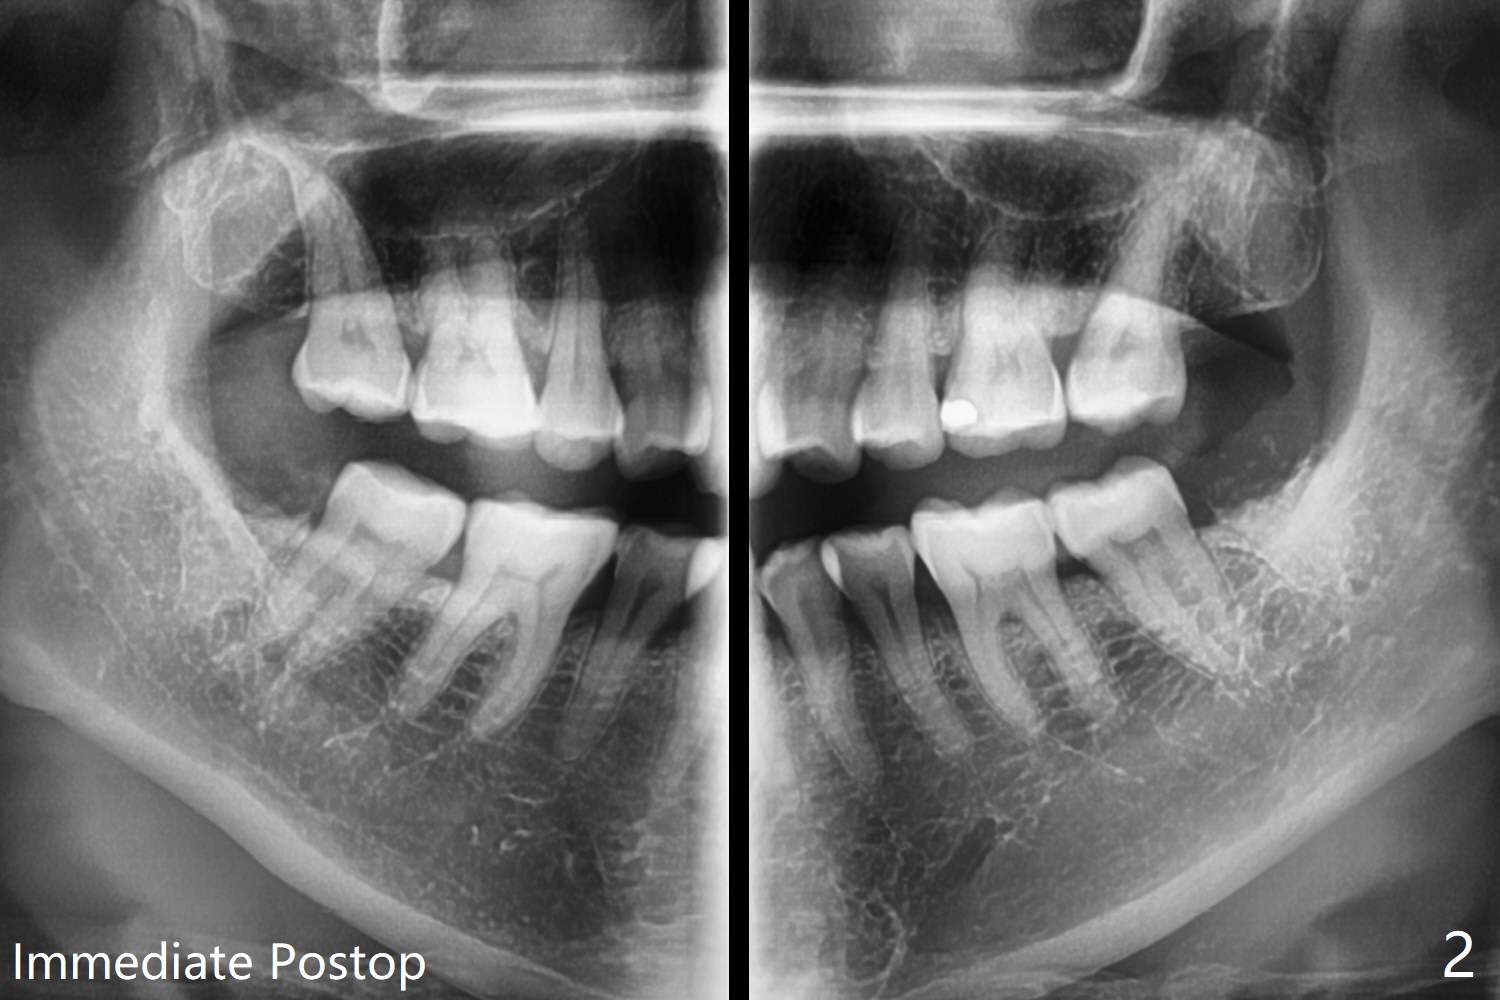

51岁女年终有多余的钱,想拔除左下智齿(早期龋齿),经过讨论,也同意拔除右下和左上智齿(图一)。看上去所有智齿拔除容易,但是右下第二,三磨牙之间骨板薄,不敢使用牙挺,怕的是松动第二磨牙,而单纯使用牙钳无法松动智齿,只好切开,颊侧去骨,形成purchase point,牙齿顺利拔除。左下智齿也采取同样方法拔除,之后下颌牙槽窝放置0.5毫升Bond Apatite和半块胶原塞,PGA多针缝合(图二),术后口服Amoxicillin。术后第四天左下出现典型干槽症症状,第七天就诊,缝线溶解,牙槽窝似乎是空的,生理盐水冲洗,改善不大,而右下缝线仍在,伤口愈合正常。拍摄局部全景片(图三),左下牙槽窝上半部好像失去骨水泥。疑问:局麻下,再次清创,放置粘性骨粉和PRF膜,能改善症状?伤口需要减张缝合(第一次和这次,periosteum underscoring)?